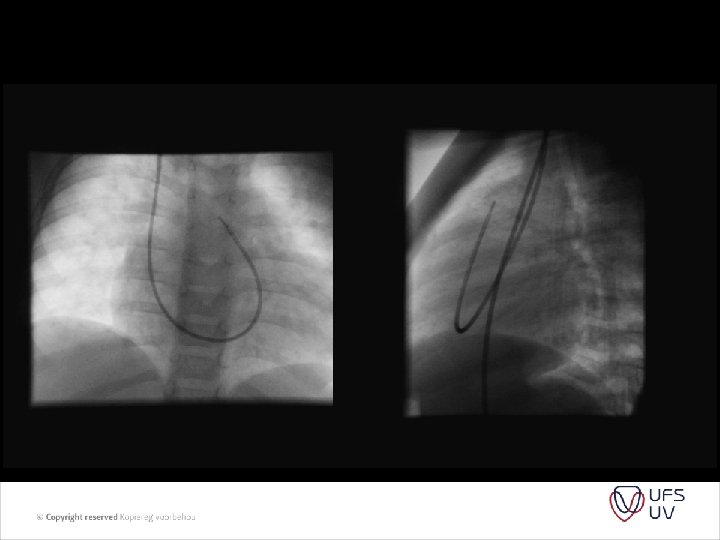

HOW TIGHT SHOULD THE BAND BE? • Trusler formula - early 1972 • A method of banding the pulmonary artery for large isolated ventricular septal defect with and without transposition of the great arteries. Trusler GA, Mustard WT. I - noncyanotic nonmixing lesions - 20 mm + 1 mm/kg II - Mixing lesions (TGA+VSD) - 24 mm + 1 mm/kg III - Single ventricle for Fontan - 22 mm + 1 mm/kg

• Intra-op pressure and saturation monitoring , aim to lower PAP to normal or ½ of systemic without desaturation or bradycardia - many variable factors - GA - Mechanical ventilation - Open chest - Days after op when hematocrit / p. H ext. • Determine Qp/Qs after Trusler formula was used. • Site of placement – mid MPA trunk